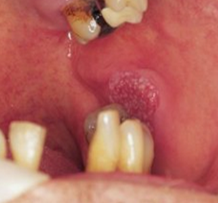

(i) Oral Squamous Cell Carcinoma |

The following clinical photographs indicate some of the more common presentations of oral squamous cell carcinomas. |

| Left buccal mucosa - speckled patch. |